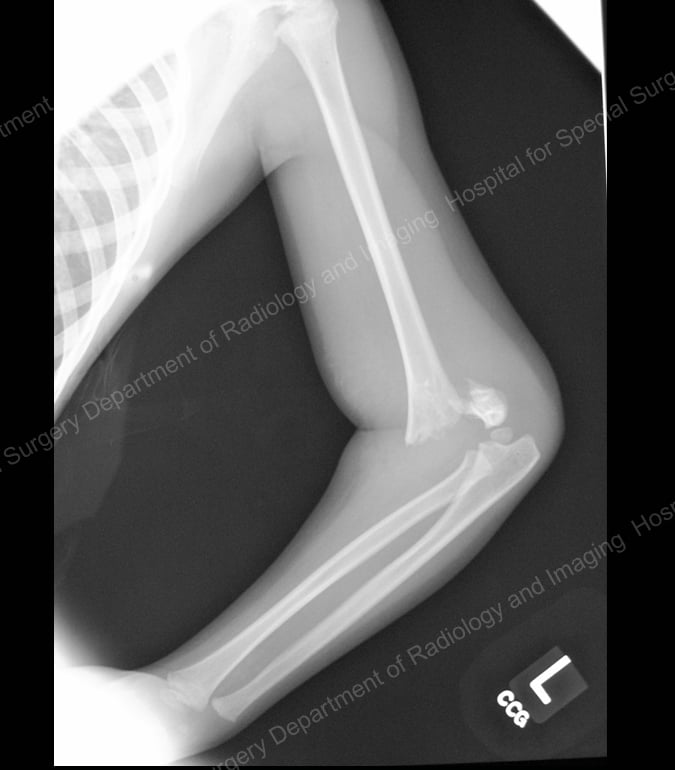

Seen primarily in younger children – ages four to eight years – these are the most common type of elbow fracture seen by pediatric orthopedic surgeons. This break occurs in the humerus bone just above the elbow joint.

Figure 1: Lateral (side) X-ray of a supracondylar humerus fracture.

Because the brachial artery (the main artery in the upper arm) and the nerves that control movement of the hand sit along this bone, these fractures are also associated with an increased risk of vascular and nerve injury.